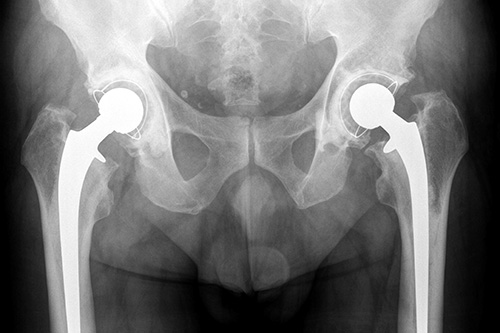

Wissenschaftler der FAU arbeiten gegenwärtig an einer Möglichkeit, um die hochentwickelte Röntgentechnik noch einen Schritt weiterzubringen. Mittels Röntgen-Dunkelfeldbildgebung wollen die Forscher 3-dimensionale-Rekonstruktionen vom Materialaufbau gescannter Objekte anfertigen, die neuartige Informationen über die Materialstruktur liefern.

Das Verfahren soll zukünftig in der medizinischen Bildgebung und der zerstörungsfreien Prüfung im industriellen Rahmen zum Einsatz kommen, um Veränderungen in der Struktur von Material oder menschlichem Gewebe besser untersuchen zu können.

Die sogenannte Röntgen-Dunkelfeldbildgebung ist eine relativ neue Möglichkeit, um den Aufbau eines Materials auf kleinster Ebene, genauer gesagt, kleiner als die mögliche Auflösung eines Röntgenbildes und damit kleiner als ein Pixel, visuell zu untersuchen. Dies ist durch einen sogenannten Talbot-Lau-Messaufbau möglich.

Das Ergebnis sind drei verschiedene Bildtypen: das allgemein bekannte Röntgenbild, das die Absorption der Strahlung zeigt, ein sogenanntes Phasenkontrastbild und das Dunkelfeldbild. Während man beim Phasenkontrastbild die sehr kleinen Richtungsänderungen der Röntgenstrahlen beim Durchdringen von Materie nutzt, um Objekte sichtbar zu machen, beschreiben Dunkelfeldbilder Unregelmäßigkeiten in den Röntgenwellen, die von kleinen Objektstrukturen unterhalb der Pixelgröße verursacht werden.

Es liefert somit Informationen über Schwankungen in Struktur und Dichte des untersuchten Materials. Mit diesem Verfahren können kleinste Veränderungen im Material sichtbar gemacht werden, wie zum Beispiel Mikrorisse. Aber auch in der medizinischen Röntgendiagnostik kommt diese Methode zum Einsatz, da sich so zum Beispiel krankhaftes von gesundem Gewebe besser unterscheiden lässt.

In Erlangen rekonstruieren die Wissenschaftler nun aus den Dunkelfeldbildern dreidimensionale Ansichten. Dazu entwickelt das Team um Prof. Gisela Anton vom Lehrstuhl für Teilchen- und Astroteilchenphysik der FAU einen Talbot-Lau-Röntgenaufbau, um mit einer einzigen spiralförmigen Bahn das Untersuchungsobjekt zu scannen. Die Informatiker schreiben hierzu die nötigen Algorithmen. Aus den daraus gewonnenen Informationen werden dann die 3-dimensionalen Objekt-Rekonstruktionen angefertigt.